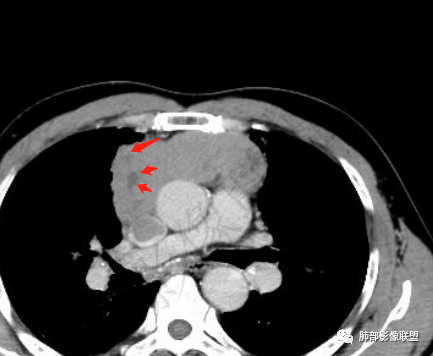

2.上纵隔增宽并见不规则块影,密度不均,轻度不均匀强化,隐约见液化密度区。

病灶边界不清,轻度分叶,后方部分紧密包绕升主动脉且侵入上腔静脉及左无名静脉末端,相应上腔静脉及左无名静脉管壁不完整。

▲上腔静脉内瘤栓

▲病灶骑跨在主动脉前缘,主动脉包绕

晨读病例:男性患者,60岁,面部肿胀一月入院,影像表现,前纵隔实性肿块影,密度均匀,部分层面与腔静脉分界欠清晰,增强扫描病灶轻度强化,病灶内可见低密度无强化区,上腔静脉受侵犯,右侧肺门,纵膈淋巴结增大,考虑恶性病变,胸腺癌>侵袭性胸腺瘤,鉴别淋巴瘤。

面部肿胀(腔静脉阻塞综合征),前纵隔实性肿块,密度均匀,分叶,病灶内多个低密度区,与腔静脉分界不清晰,增强病灶轻度强化,肺门,纵膈淋巴结增大,胸腺癌?